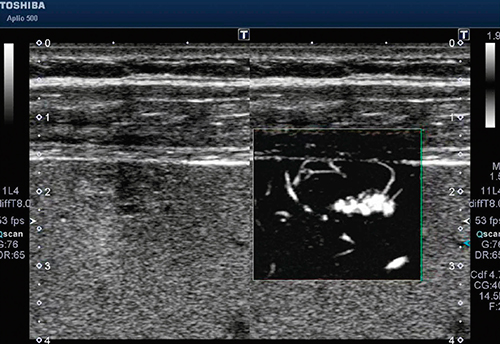

従来の血流イメージング機能では,低流速域の血流描出を行う際に,血流以外の対象物からの不要なドプラ信号(モーションアーチファクト)に血流信号が埋もれてしまい,モーションアーチファクトを除去するために低流速域の血流情報を同時に失っていた。これに対し,SMIはモーションアーチファクト特有の特徴を解析し,選択的に除去することにより,低流速域の血流情報を損なうことなく表示することが可能となった(図4)。非造影でも低流速血流を高精細に描出することができ,また超音波造影剤とSMIを組み合わせることで,従来の造影超音波よりさらに高感度に低流速血流を映像化することができる。

新技術SMIは,低流速検出能に優れた血流イメージングを提供することが可能である(図5)。従来では描出できなかった血流を高精細・高フレームレートに描出することにより,腫瘍性病変などの早期診断や治療方針の決定などをサポートし,確かな診断に寄与する。

図5 SMIによる肝血管腫:血流像

(画像ご提供:成田赤十字病院・長谷川雄一先生)